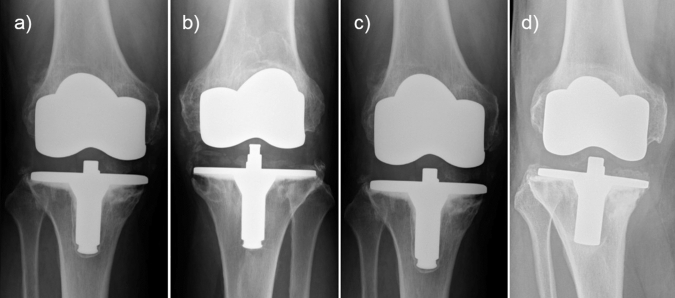

Total revision surgeries were performed in 5 knees, all in the high flex group (16.7%). One patient of the high flex group had a painful mid-flexion instability that needed to be revised after 5 years. The mean revision rate due to aseptic loosening was 4 of 30 knees (13.3%) and all were men. Because of symptomatic aseptic loosening of the cemented tibial prosthesis, four high flex knees were revised after 7, 8, 14 and 16 years. In the AP view, tibial radiolucent lines were found just in zone 1 for two knees, zone 1 and 5 in a second knee and another showed a progressive lucency in all zones with dislocation, as described in the Knee Society Roentgenographic Evaluation and Scoring System (Fig. 1). There was no noticed revision in the LPS group.

Fig. 1.

High-flex knees with aseptic loosening of the cemented tibial prosthesis after a 7 years (zone 1 and 5), b 8 years (zone 1), c 14 years (zone 1), and d 16 years (all zones with dislocation) using the Knee Society Roentgenographic Evaluation and Scoring System